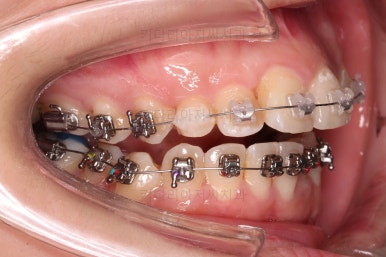

초진 시 입안의 모습입니다.

앞니쪽이 조금 삐뚤어 보인다는 점 이외에는 큰 문제점이 보이지 않죠?

어금니쪽을 자세히 관찰해 보면, 위아래 어금니의 맞물림(교합)이 어긋나 있는데요.

톱니바퀴처럼 물려야 되는 교합이 한 칸 씩 윗니가 아랫니보다 앞으로 나가있는 앵글씨 2급 부정교합 상태였습니다.

장치를 구성합니다.

이번 환자분은 윗니는 세라믹, 아랫니는 메탈 장치를 선택하셨는데요.

둘 다 물론 자가결찰 장치였고요.

동일한 제품의 장치이므로 혼용해서 쓰는게 가능합니다.

많이 보이는 부분은 세라믹, 잘 안보인다고 여겨지시는 부분은 메탈로 선택하면서 치료비 측면도 함께 고려한거죠.

장치 부착 직후의 모습인데요.

보이는 느낌과 장치 때문에 약간 더 튀어나오는 입매 참고 바랍니다.